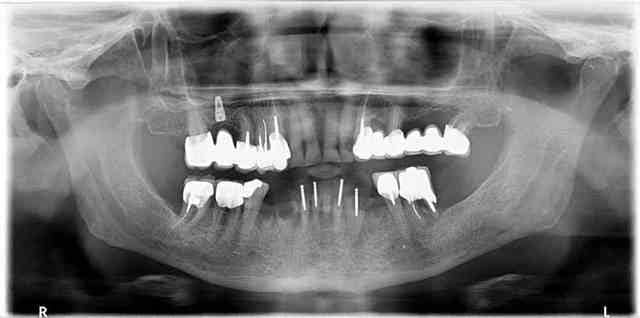

> Je vous mets en pièce jointe un Compte rendu de consultation qui est la

> propriété du patient à la suite de votre consultation... vous ne pouvez pas lui

> opposez le fait de ne pas lui donner ces informations.

> 2 mois plutot j'avais reçu un autre patient hospitalisé 15 jours pour

> pancréatite aigue médicamenteuse suite à prescription de 4 mois d'antibiotique

> du même praticien pour couvrir ses merdes...

> Le patient pour lequel j'ai mis les photos n'en était qu'à sa 3ème cure d'ATB

> pour le secteur 1... Le praticien lui disait juste qu'il temporisait pour

> réaliser le bridge.

Sur le cas illustré on ne parle plus de confraternité : il faut à tout prix empêcher ce genre d'individu de continuer à nuire , nuire à ses patients et nuire de par sa pratique à l'ensemble de la profession !

Ce gars là n'a aucun scrupule ou aucune compétence ou les 2 , ce n'est pas un confrère point à la ligne.

Et pour illustrer mes propos voici quelques photos issus du book of horror que je suis en train de me constituer.

Quand vous tombé là-dessus, quelle est votre réaction? Et surtout quand ça a été commis dans votre propre cabinet pour une somme indécente. Le patient vous demande de finir le travail alors qu'il a déjà dépenser une fortune pour ce résultat. Et il faut prendre en compte le fait que des patients dans cet état j'en ai des dizaines elle que le gars qui a fait ça n'a en aucun cas l'intention de rembourser quoi que ce soit.

Vous voyez, on est loin du niti pété ou de la couronne débordante... Et le monsieur est expert devant les tribunaux...